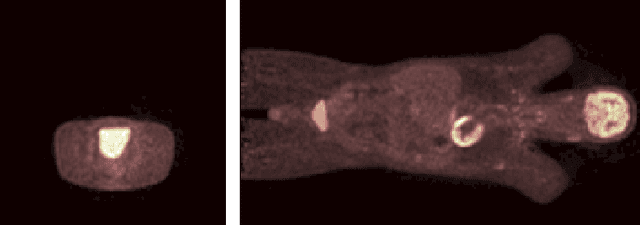

Images from positron emission tomography (PET) provide metabolic information about the human body. They present, however, a spatial resolution that is limited by physical and instrumental factors often modeled by a blurring function. Since this function is typically unknown, blind deconvolution (BD) techniques are needed in order to produce a useful restored PET image. In this work, we propose a general BD technique that restores a low resolution blurry image using information from data acquired with a high resolution modality (e.g., CT-based delineation of regions with uniform activity in PET images). The proposed BD method is validated on synthetic and actual phantoms.